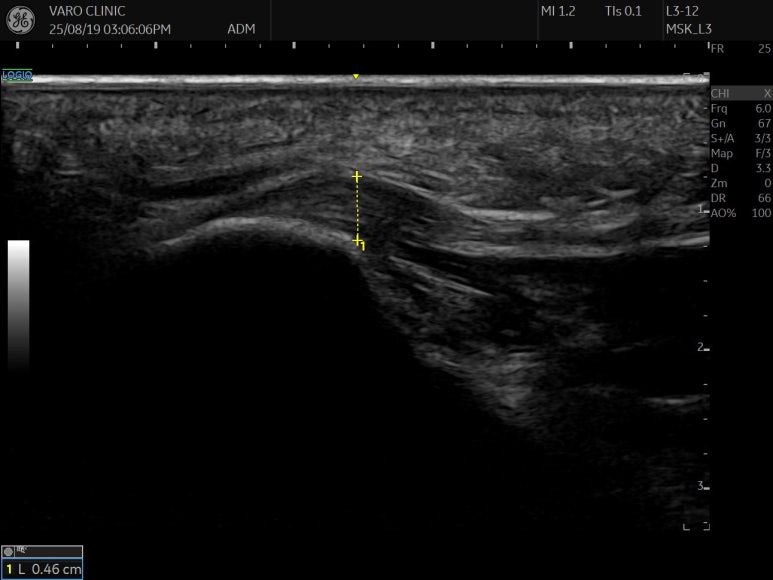

정상적인 족저근막은 초음파 영상에서 3-4mm 이하의 두께로 가지런한 섬유 다발 구조를 보이는 반면,

족저근막염이 생기면, 즉, 밧줄이 낡고 부어오르게 되면 초음파 상에서 4mm 이상 두껍게 관찰되고 맑고 하얗던 섬유 구조가 시커멓게 변하는 '저에코' 소견을 보입니다.

초음파로 을 관찰하면서

두꺼워지고 어둡게 변성된

족저근막 부위를 정확히 찾아낸 뒤,

그곳에 조직의 재생을 돕고

통증을 줄이는 약침을 정확하게 주입하는 겁니다.